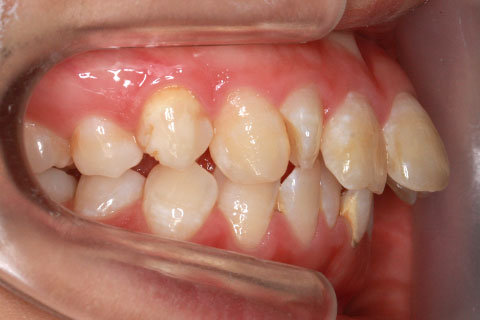

ハーフリンガル矯正3:上の歯のみ舌側矯正で治療(矯正期間24ヶ月)

治療前

治療中(開始直後)

治療中(開始半年後)

治療後

- 年齢・性別

- 25歳女性

- 治療期間

- 2年0ヶ月

- 抜歯

- 上下4番抜歯

- 治療費

- 110万円

- 治療内容

- 施術の副作用(リスク)

- 表側矯正と比較して、力学的な操作性が複雑なため、ボーイングエフェクトを起こしやすい。